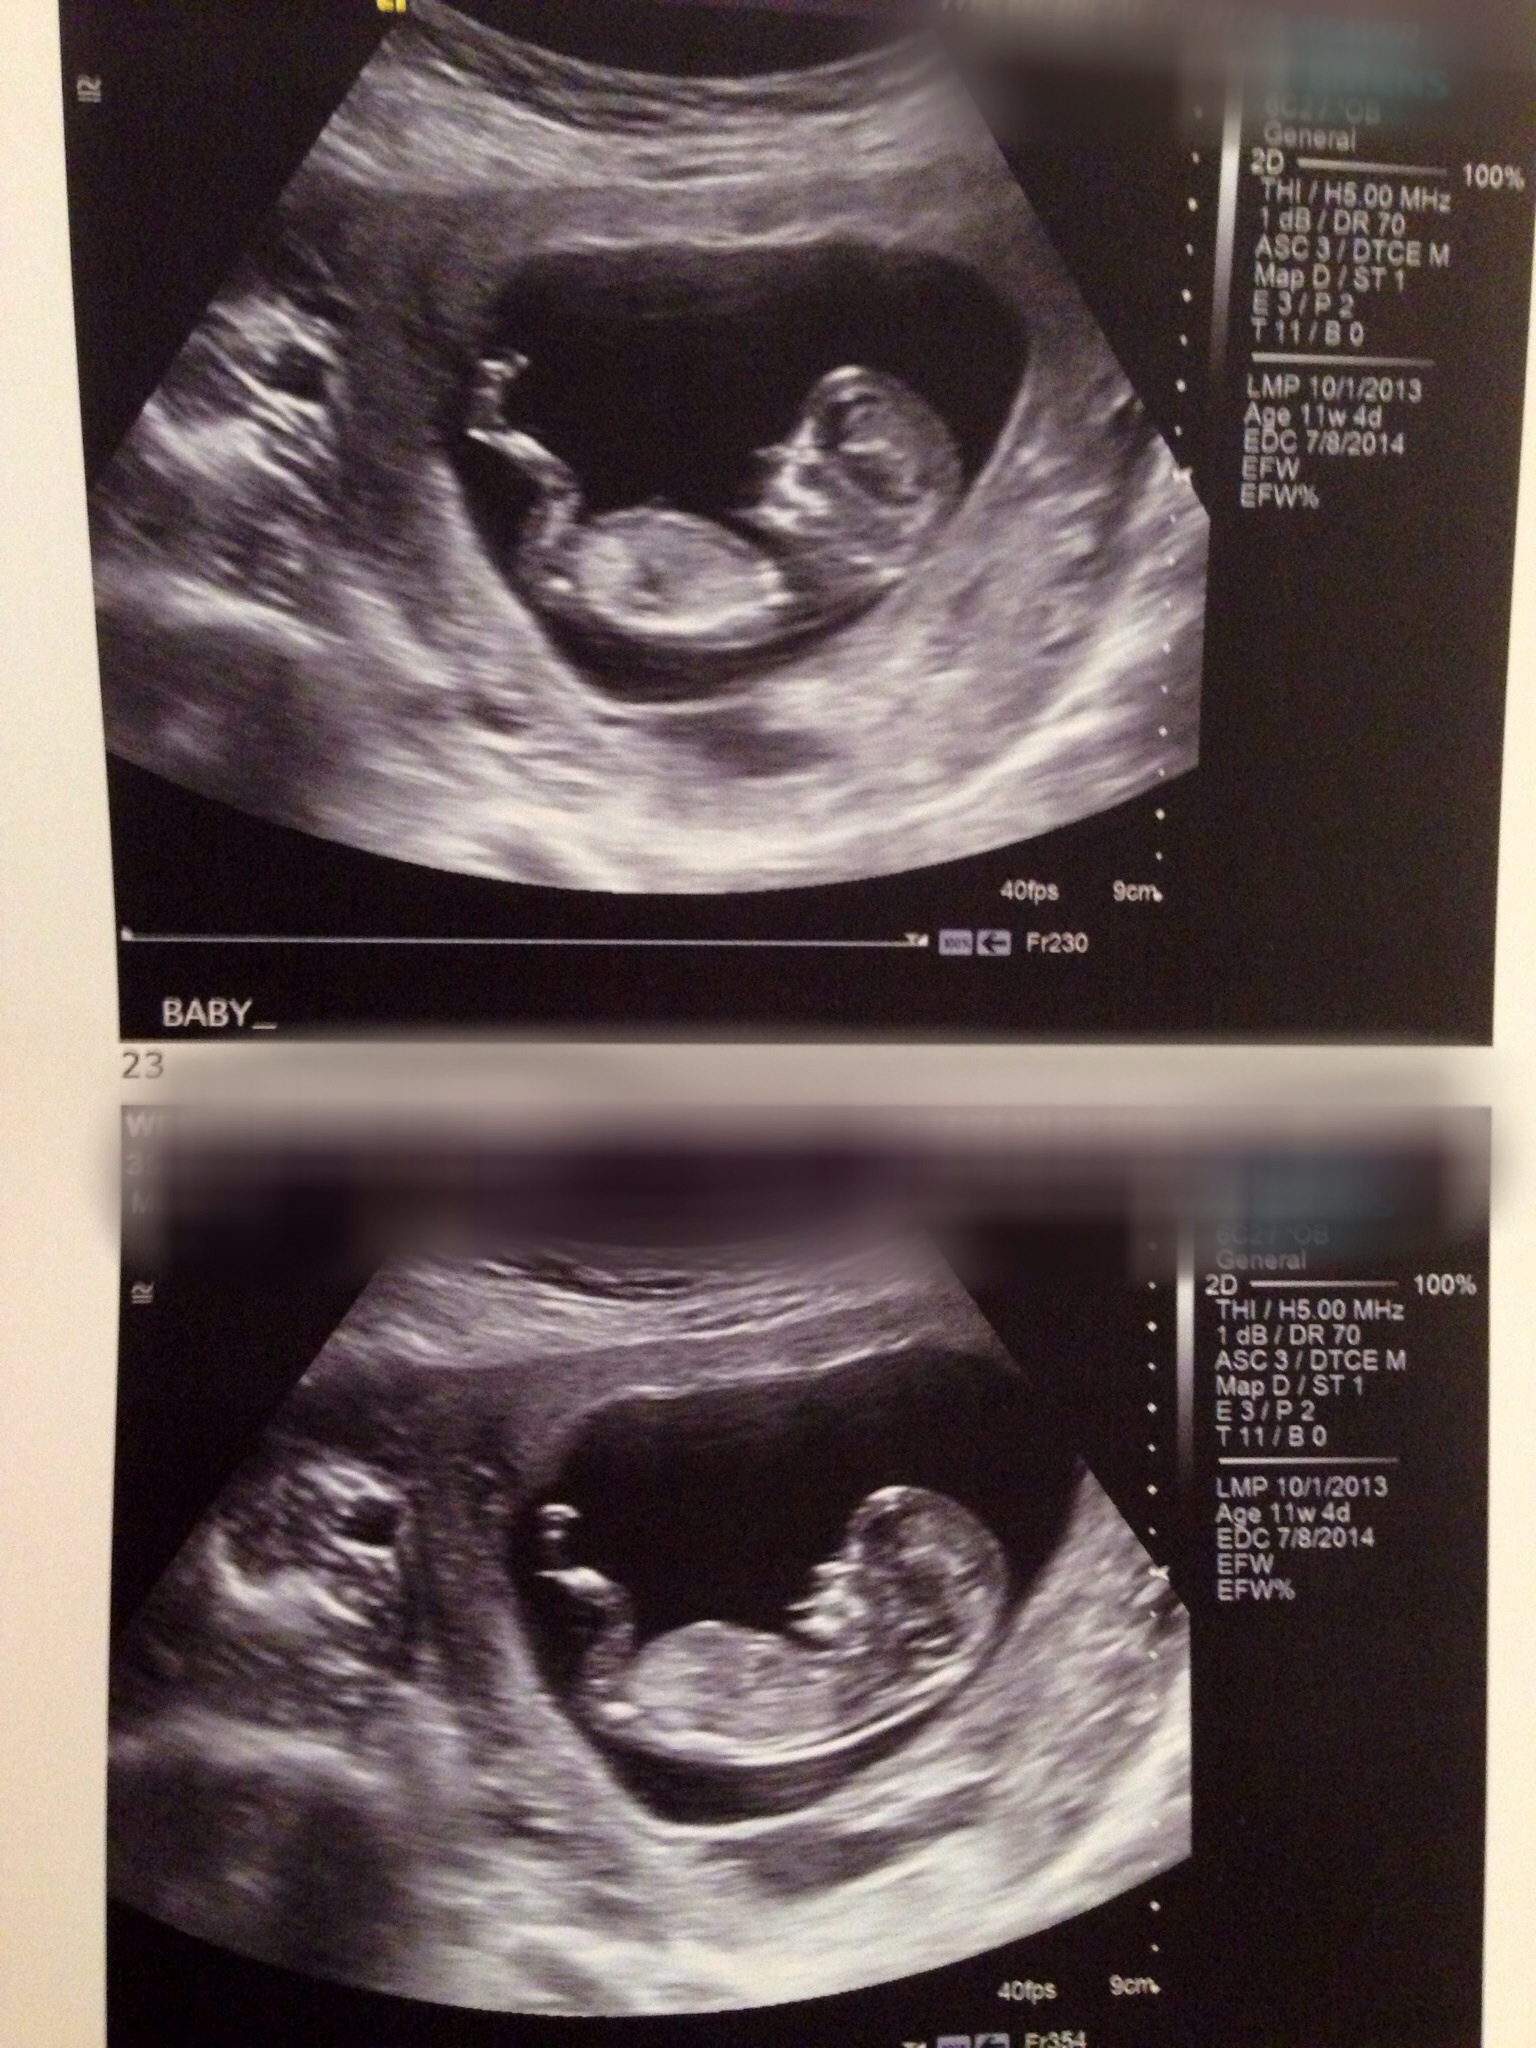

My next scan is at 13 weeks and I will get a nub shot but do any of you have guesses on the skull?! Thanks ladies!! :)